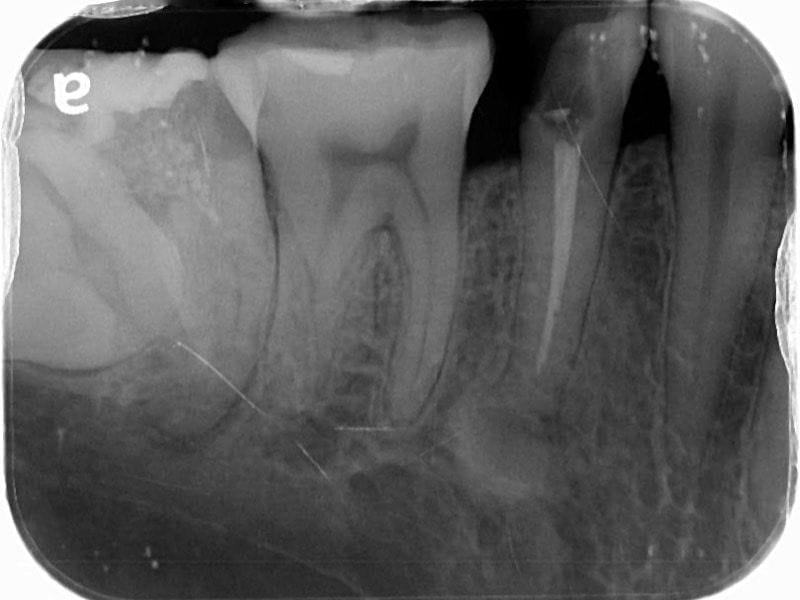

通常我們在初次看診,會針對患者主訴不適的位置優先檢查以外,也會仔細的評估全口有無其他問題。因此我們拍攝了局部疼痛位置的X光片和環口式X光片,才能了解整體的狀況。

圖示:初步看診時Mr.Su主訴不適位置的X光照,右下第二小臼齒根管治療未修復而導致牙齒斷裂

疼痛的右下第二小臼齒,早年根管治療後因未做完整的修復,牙齒發生斷裂情況;且牙齒的結構不足,導致無法保留,因此建議牙齒拔除。